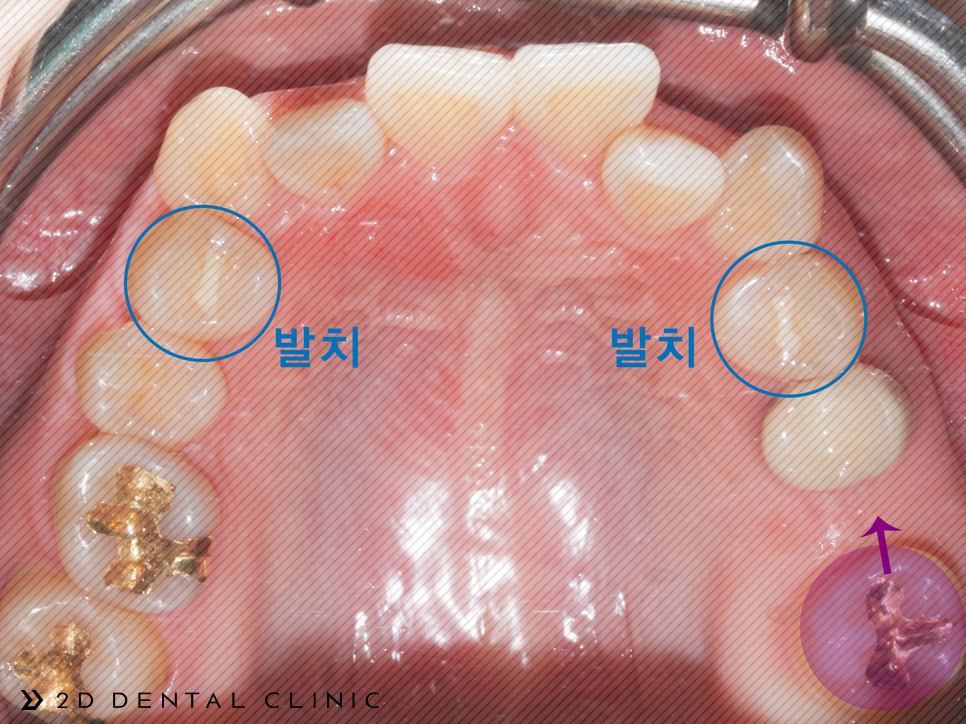

전체 교정인 클리피씨로 진행되었고 상악의 양쪽의 제1소구치를 발치하였습니다. 제2 대구치는 미니스크류로 당겨드렸고요.

전체적인 크라우딩의 개선

교정기간은 1년 반이 소요되셨답니다~ 전체적인 크라우딩이 개선되고 치아 배열이 고르게 개선되었습니다.

코와 턱 이어지는 E라인을 잡아드려 퉁명스러울 수 있는 인상이 개선됨이 보입니다.